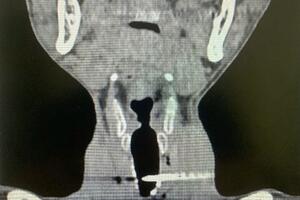

![]() |

Bỏng da do nắng nóng. Ảnh minh họa: anninhthudo.vn |